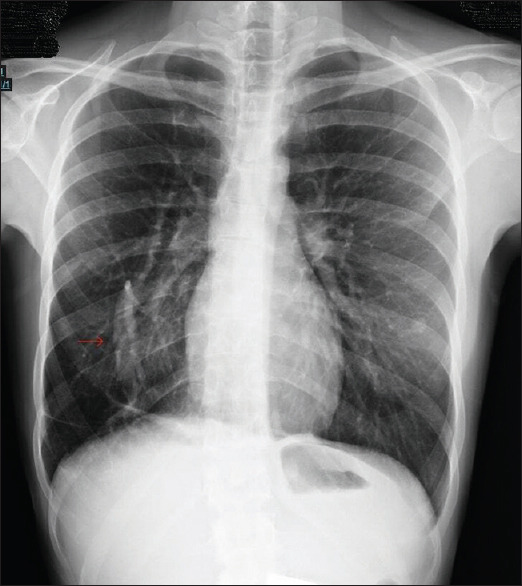

Abstract: Welcome to this radiology challenge. Follow the clues to diagnose a young woman presenting with an unusual and persistent cough. Let us dive into the clinical case and see if you can figure out the cause.